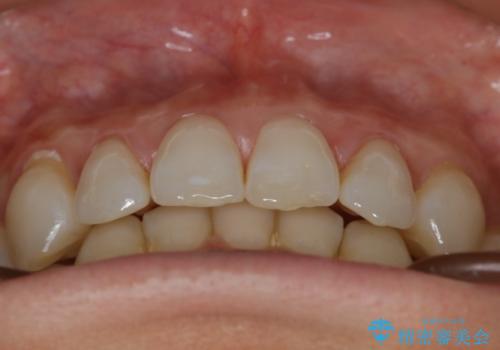

【抜歯】矯正治療とインプラントで正常な噛み合わせを実現

- 元々は矯正治療を主訴にご来院されました。

治療を始めるにあたり、精密検査を受けていただき全体の状況を把握したうえで矯正治療の計画を立てることとなりました。

その過程で左下の6番目の歯は治療が必要な状態であることが分かり、被せ物を外して内部を確認してみると根が破折してしまっていることが判明しました。

歯が深い位置で破折している場合は基本的には抜歯が選択されます。

様々な治療プランを患者さんと相談させて頂き、最終的にインプラントで噛み合わせを回復させていくこととなり、まず悪くなっている歯を抜歯することから開始しました。